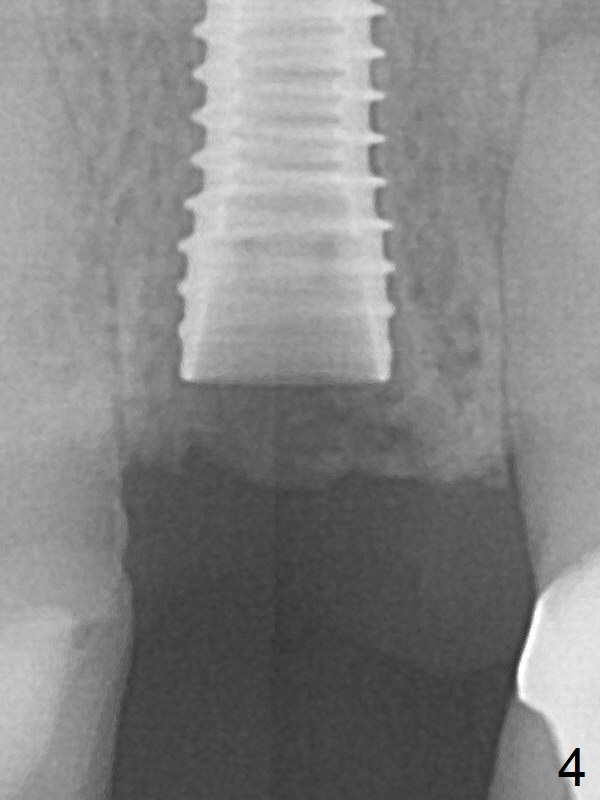

A 3.8x16 mm implant is placed (Fig.4 (with 2 mm buccal gap)) at the level as planned (Fig.2). Insertion torque is acceptable. After placing a 4.5x5(3) mm gold-coated abutment and allograft (Fig.5), an immediate provisional is fabricated (the existing crown is lost). The patient is pleased with the quick, painless procedure.